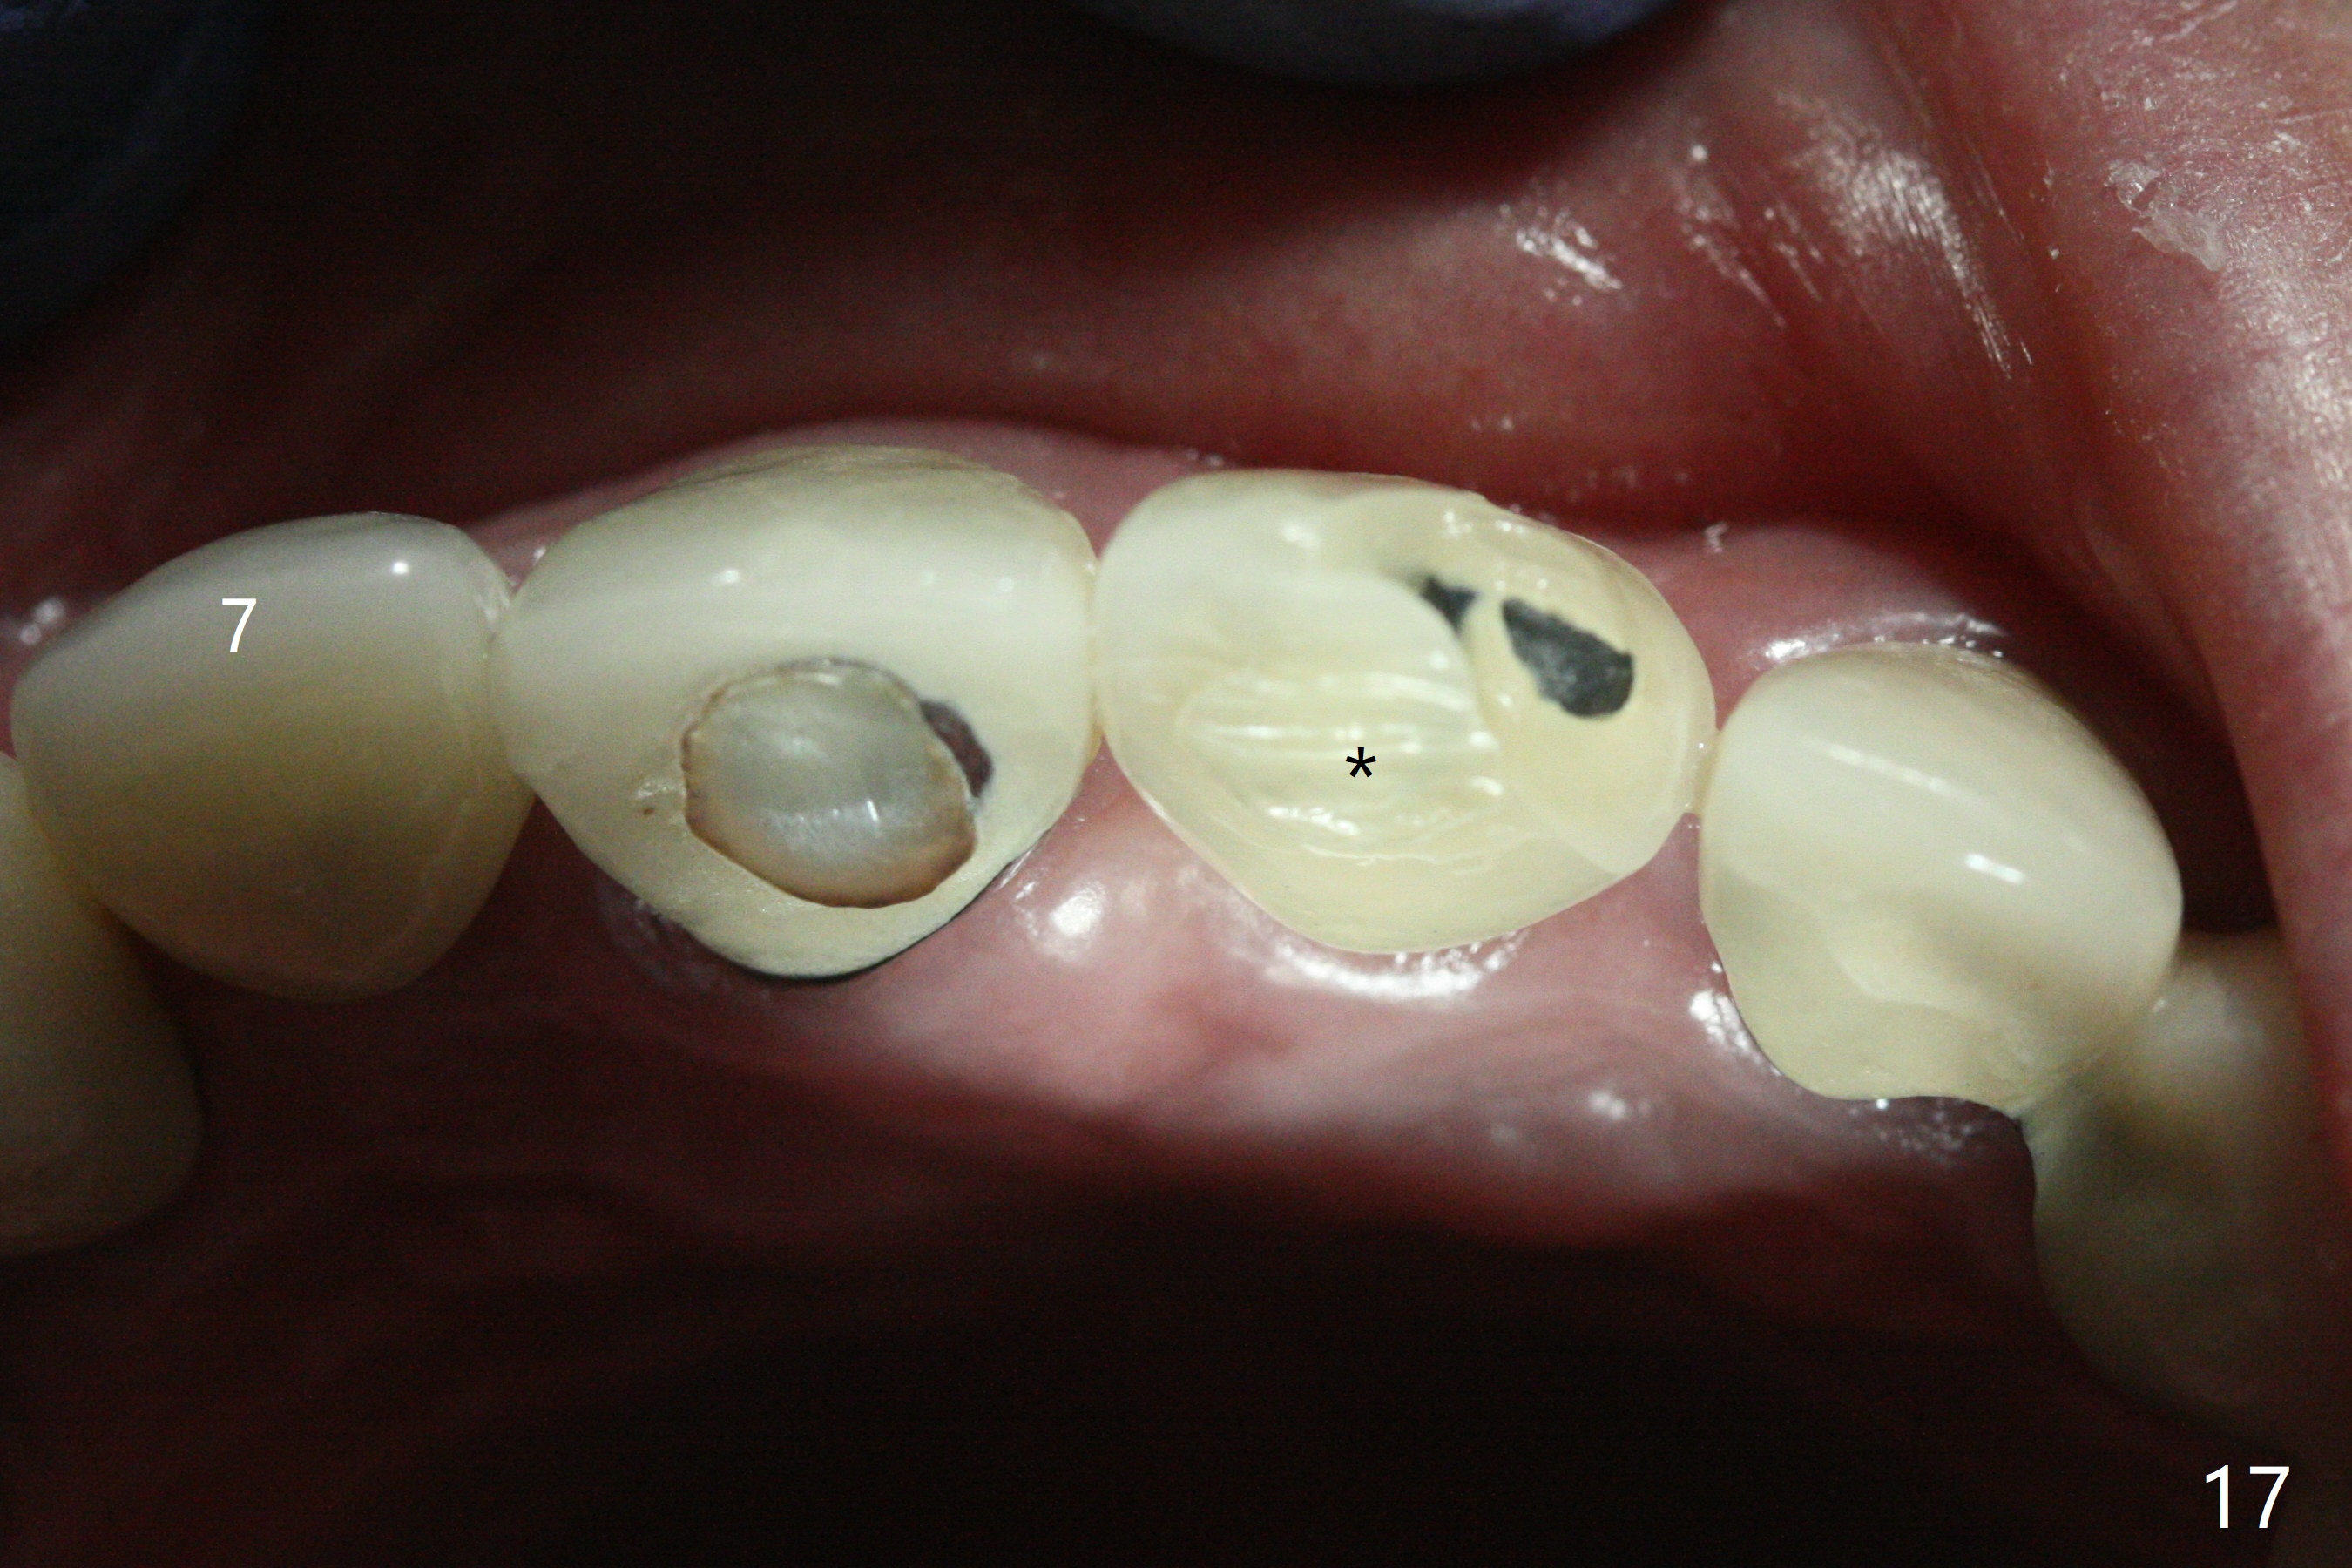

The buccal contour at #9 seems to be slightly concave preop (Fig.1,2 (*)). In fact the buccal plate is found to be lost when the tooth is extracted. Osteotomy is initiated as palatal as possible apical, but the occlusion dictates the coronal end of the osteotomy should be buccal, leaving the buccal gap ~ 2 mm for bone graft. The initial osteotomy (18 mm deep) appears to be close to the Incisive Foramen (Fig.3 blue dashed line). The nasal floor appears to be intact when the drill is removed. Subsequent osteotomy is adjusted so that the apical end of the osteotomy moves distal; when a 3.8x15 mm dummy implant is partially placed, there is clearance (Fig.4). It remains so when a definitive implant is seated (Fig.5); Vanilla graft is placed (Fig.5 *) before placement of a 4.5x5.5(3) mm abutment. More allograft is placed when an immediate provisional is fabricated (Fig.6 arrow and *). The gingiva remains to be recessive 1 month postop (Fig.7). It seems to be related to the bulky gingival margin of the provisional (Fig.8 *). After trimming the latter (Fig.9 *), the gingival margin immediately returns close to normal (Fig.10). The gingival margin is even between #8 and 9 two months postop, but the bone graft is exposed apically (Fig.11 ^). It may heals by itself. Otherwise debridement, regraft, PRF and suture are pending. The coronal portion of the socket heals 4 months postop (Fig.12). The gingival cuff forms by the immediate provisional (which is removed for impression) 4 months postop (Fig.13 *). While the full Zirconia crown at #7 remains intact (Fig.14), the PFM at #9 has porcelain chip (Fig.15). It is partially due to the occlusion; while the crown at #7 has clearance with the opposing dentition (Fig.16 *), the one at #9 has no. The access hole at #9 (Fig.17 *) seems to weaken the crown structure. There is no access hole at #7. No solid posterior support is another contributing factor for chip (Fig.18). The buccal plate has mild atrophy at #7 and 9 (Fig.19 *). A piece of bone graft is being expelled apically at #9 (Fig.20 >) and is removed subsequently (Fig.21). Before impression for repacking porcelain, the opposing incisal edge has been shortened (Fig.22 arrows, as compared to Fig.16). Since the ideal access hole is at the incisal edge (Fig.25 black circle), buccal to the existing one (Fig.24 A), the abutment is torqued before the repaired crown is recemented (Fig.23). Finally the crown has occlusal clearance (Fig.26). Porcelain chips again around the access hole of PFM 1.5 years post 2nd cementation. The dense bone at the crest (*) cannot explain why the abutment is not loose, since it remains incompletely seated (>). As it was trimmed short, an angled abutment is used (Fig.28). The coronal end is lingual, while #9/24 is edge to edge. The lingual aspect of the coronal end of the abutment is heavily trimmed to reduce bulkiness. To prevent chip, Zirconium crown will be fabricated in spite of the fact that it does not match the PFM of #8 (potential shade discrepancy). The patient is pleased with the new Zirconia crown (Fig.29).